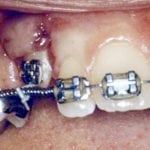

In cases where the eyeteeth will not erupt spontaneously, the orthodontist and oral surgeon will work together to get these teeth to erupt. Each case must be evaluated on an individual basis, but treatment will usually involve a combined effort between the orthodontist and the oral surgeon. The oral surgeon will expose and bracket the impacted eyetooth.

The goal is to erupt the impacted tooth and not to extract it. Once the tooth has moved into its final position, the gum around it will be evaluated. In some circumstances, there may be some minor “gum surgery” required.

Exposure and Bracketing of an Impacted Cuspid